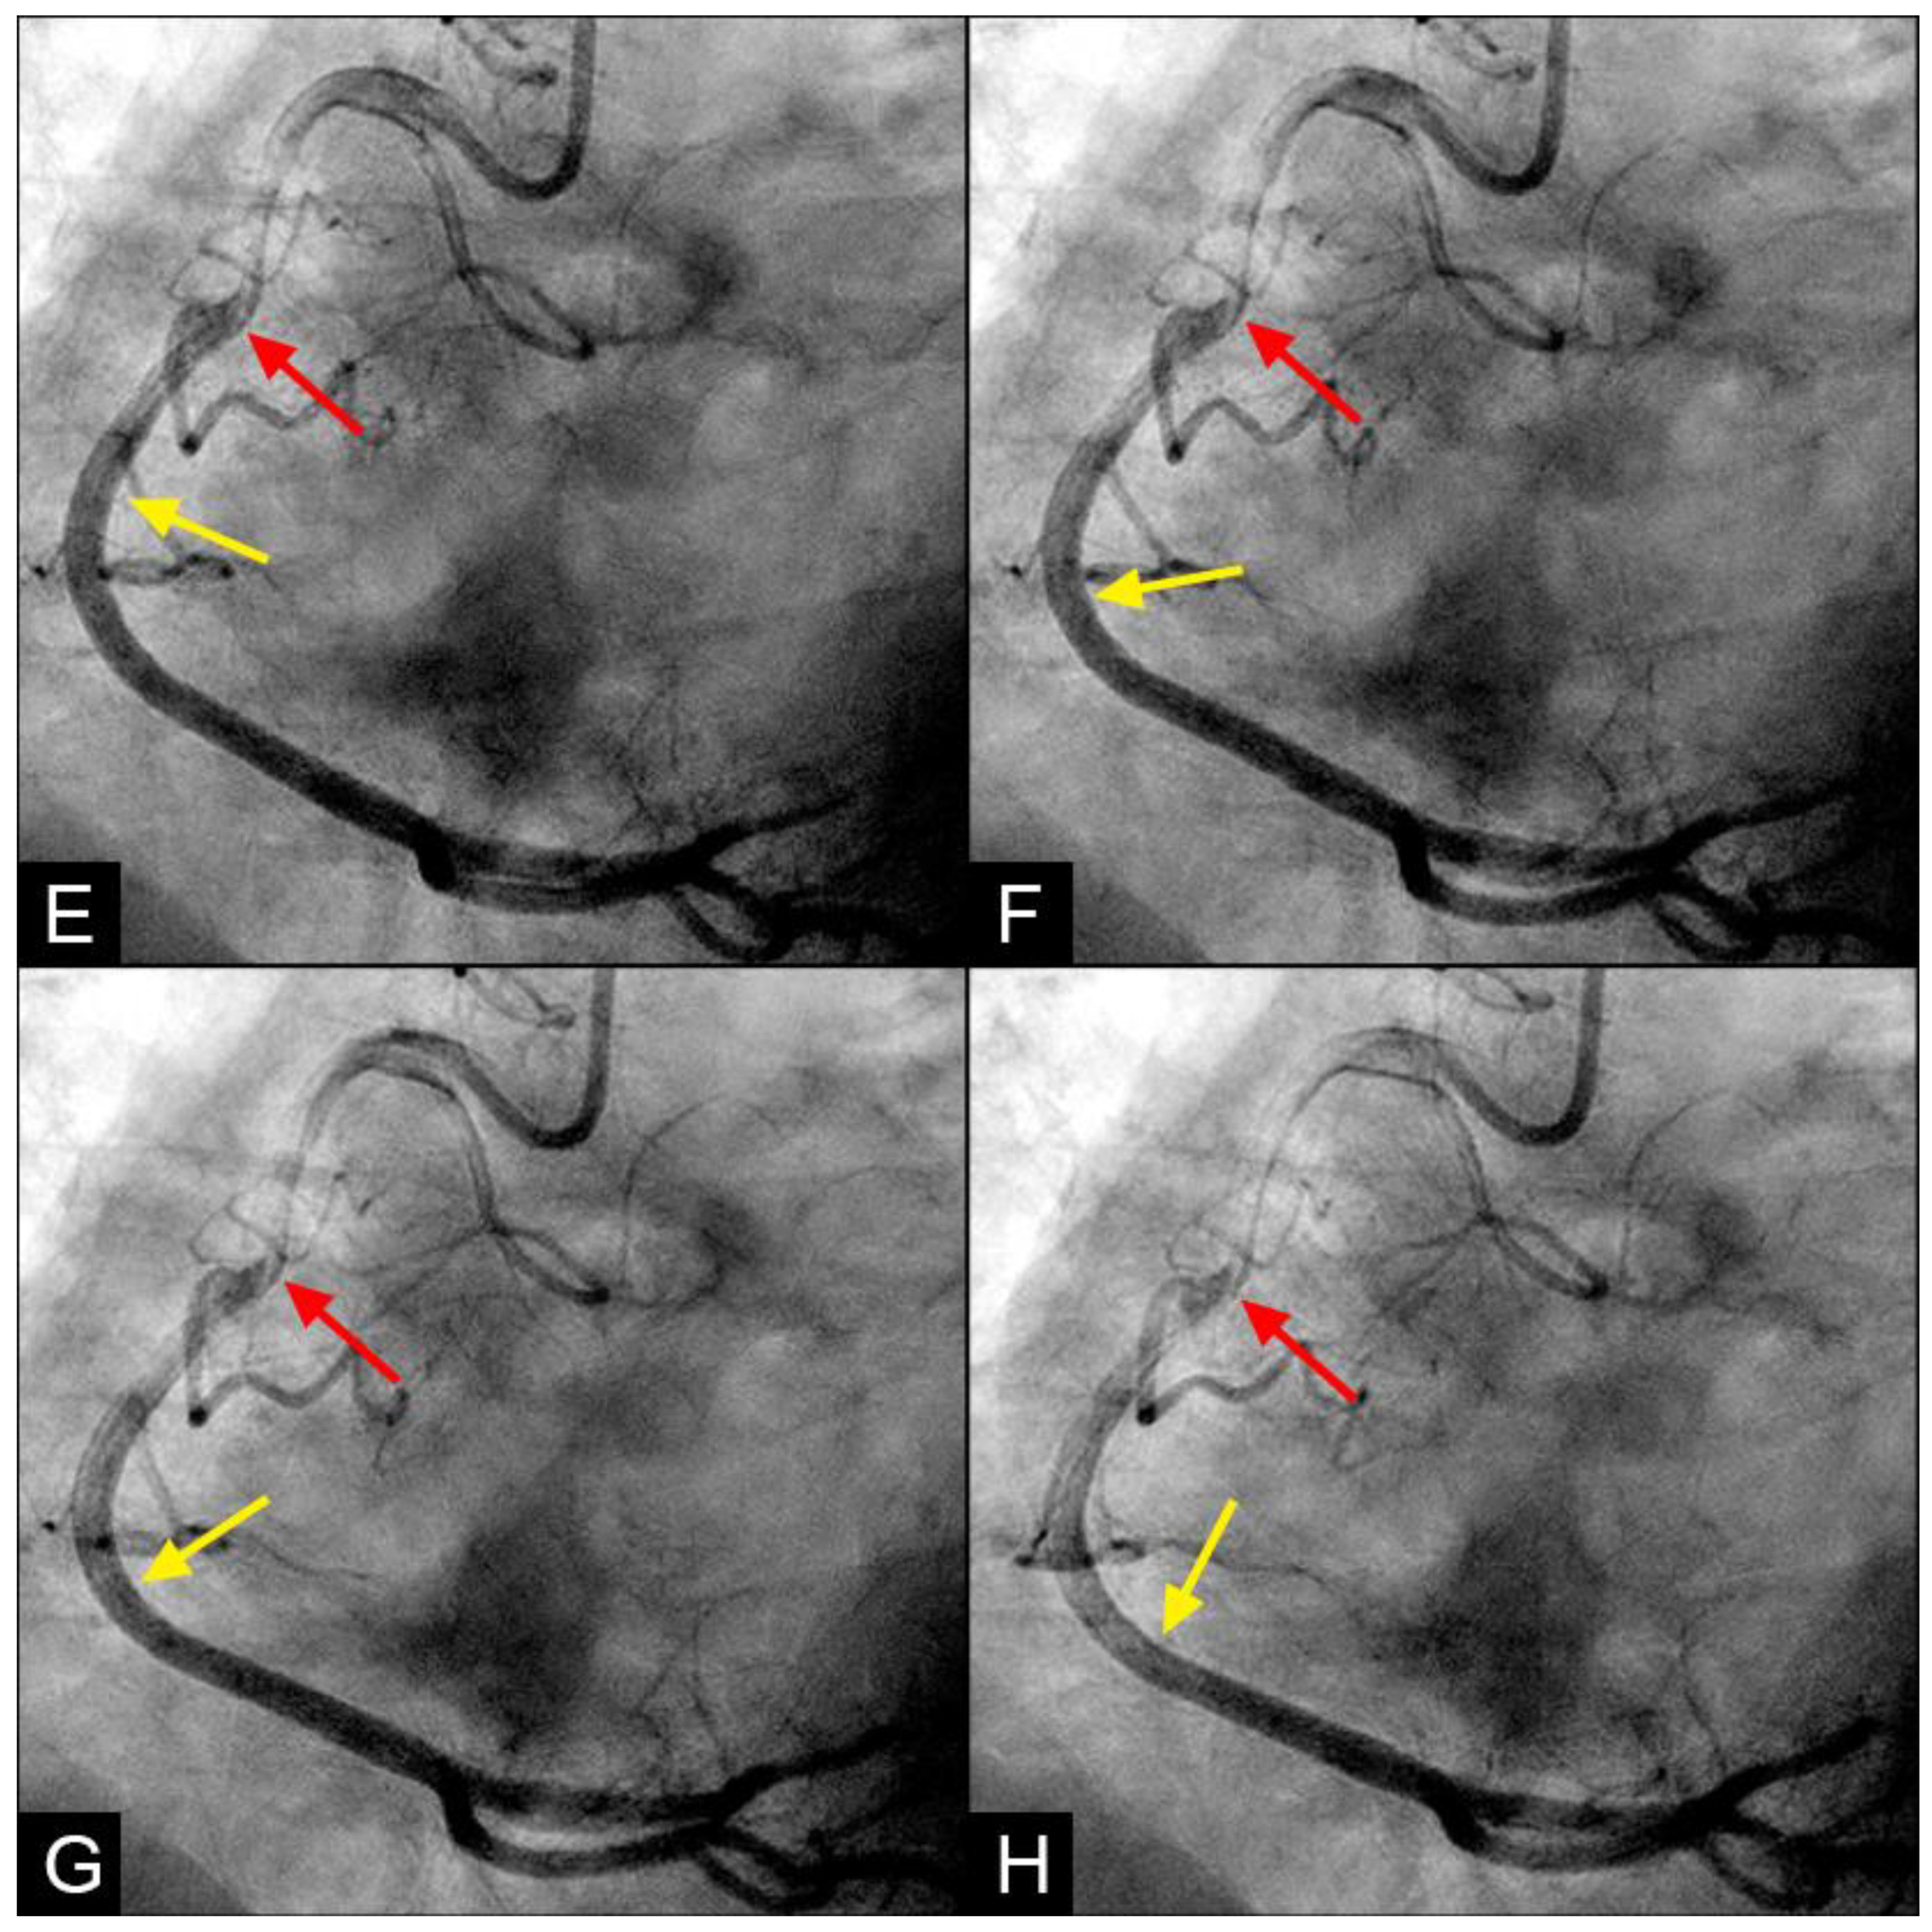

In the right coronary artery (RCA), with the novel angiographic technique, during diastole, the antegrade flow was clearly illustrated (Figure 9A–D). The leading edge of the flow was sharp, suggestive of laminar flow (Figure 9C). The speed in diastole was fast, as the blood could traverse from the end of the proximal segment to halfway through the mid-segment in just 0.067 s, equivalent to one image interval (Figure 9D). At this junction, at the onset of systole, the antegrade flow decelerated (yellow arrow), while the mixed black contrast persisted at the location of the transition from diastole to systole (red arrow). This contrast remained until near the end of systole, providing visual evidence of disorganized flow secondary to the interaction between the retrograde and antegrade flows; most likely, it was a collision (Figure 9E–H) (Video S2).

Figure 9.

(A–D) Collision in the RCA. This is a series of eight consecutive images of an angiogram of the right coronary artery (RCA). (A) The artery is filled with contrast. There is a moderate lesion at the mid-segment. (B) The blood (white) is seen entering the ostium of the RCA (arrow). This is the beginning of diastole. (C) The blood (white) is seen at the outer border of the first curve of the RCA (yellow arrow). (D) The blood (white) moves to the mid-segment of the RCA (yellow arrow). (E–H) Collision during the transition to systole. (E) The blood is seen reaching the mid-segment of the RCA (yellow arrow) at the end of diastole and beginning of systole. Here, the blood (white) is mixed with the contrast (black), seen as a random, disorganized black-and-white pattern (red arrow). This is the visual imaging of turbulent flow. (F,G) The contrast (black) concentrates at the mid-segment, at the collision line (red arrow). The contrast is also seen darker in the proximal segment, suggestive of retrograde flow. The antegrade flow still moves forward slowly (yellow arrow). (H) The blood is seen reaching the beginning of the distal segment (yellow arrow). The turbulent flow (mixing black contrast and white blood) is still seen prominently at the collision site, and the retrograde flow is lighter at the mid-segment (red arrow).